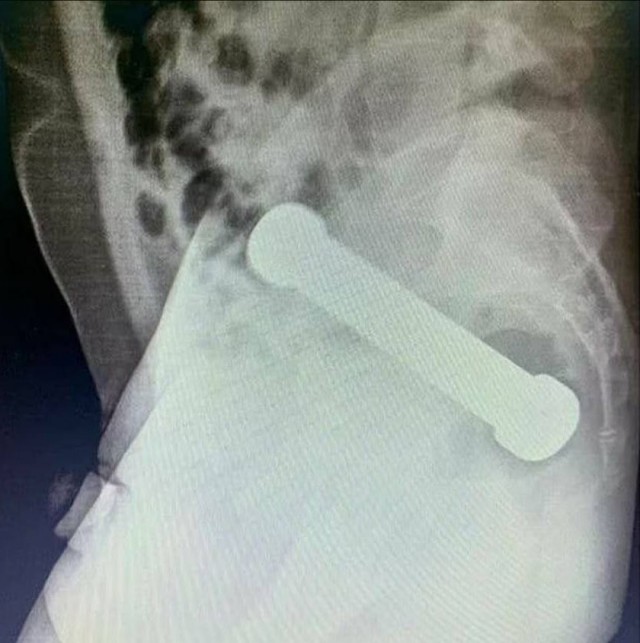

Гантеля в жопе!

Мужчина сутки ходил с кабачком в заднем проходе

В Бразилии мужик себе в жопу засунул 2-килограммовую гантелю и проходил с ней целых два дня.

54-летний анальный спортсмен обратился к врачам и заявил, что из-за болей в животе он не может посрать. Когда врачи сделали рентген – они увидели спортивный снаряд и ахуели.

По словам медиков, человек-гантеля «не проявлял готовности к сотрудничеству», поэтому его пришлось усыпить. Гантелю пытались извлечь с помощью хирургического пинцета, но не вышло — трудно подцепить и слишком тяжелая. Тогда бедным врачам ничего не оставалось, кроме как залезть в очко руками и вытащить жопный снаряд.